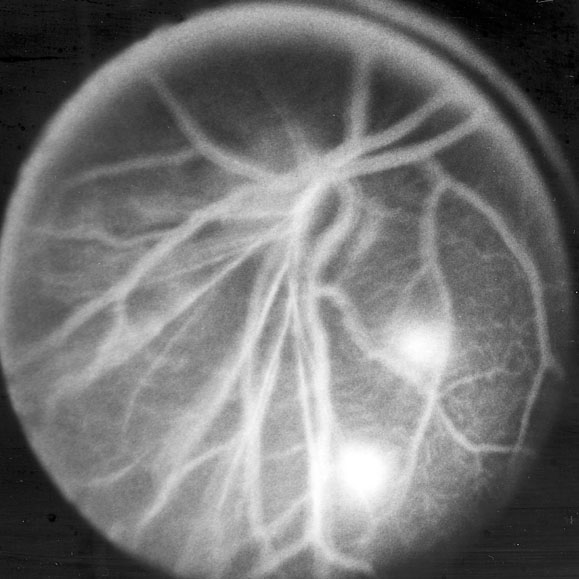

Figure 5. Fluorescein angiograms

A: Normal C57BL/6J mouse eight weeks of age, taken in early venous phase. All retinal arterioles and venules are filled with dye and details of the retinal capillary bed are easily visualized. B-D: Eight week old Onc1 mouse, demonstrating an abnormal blood vessel pattern and two areas of inferolateral fluorescein leakage that become more apparent from early to late venous stages. The angiograms in B-D were taken 143, 183, and 209 s after fluorescein administration.